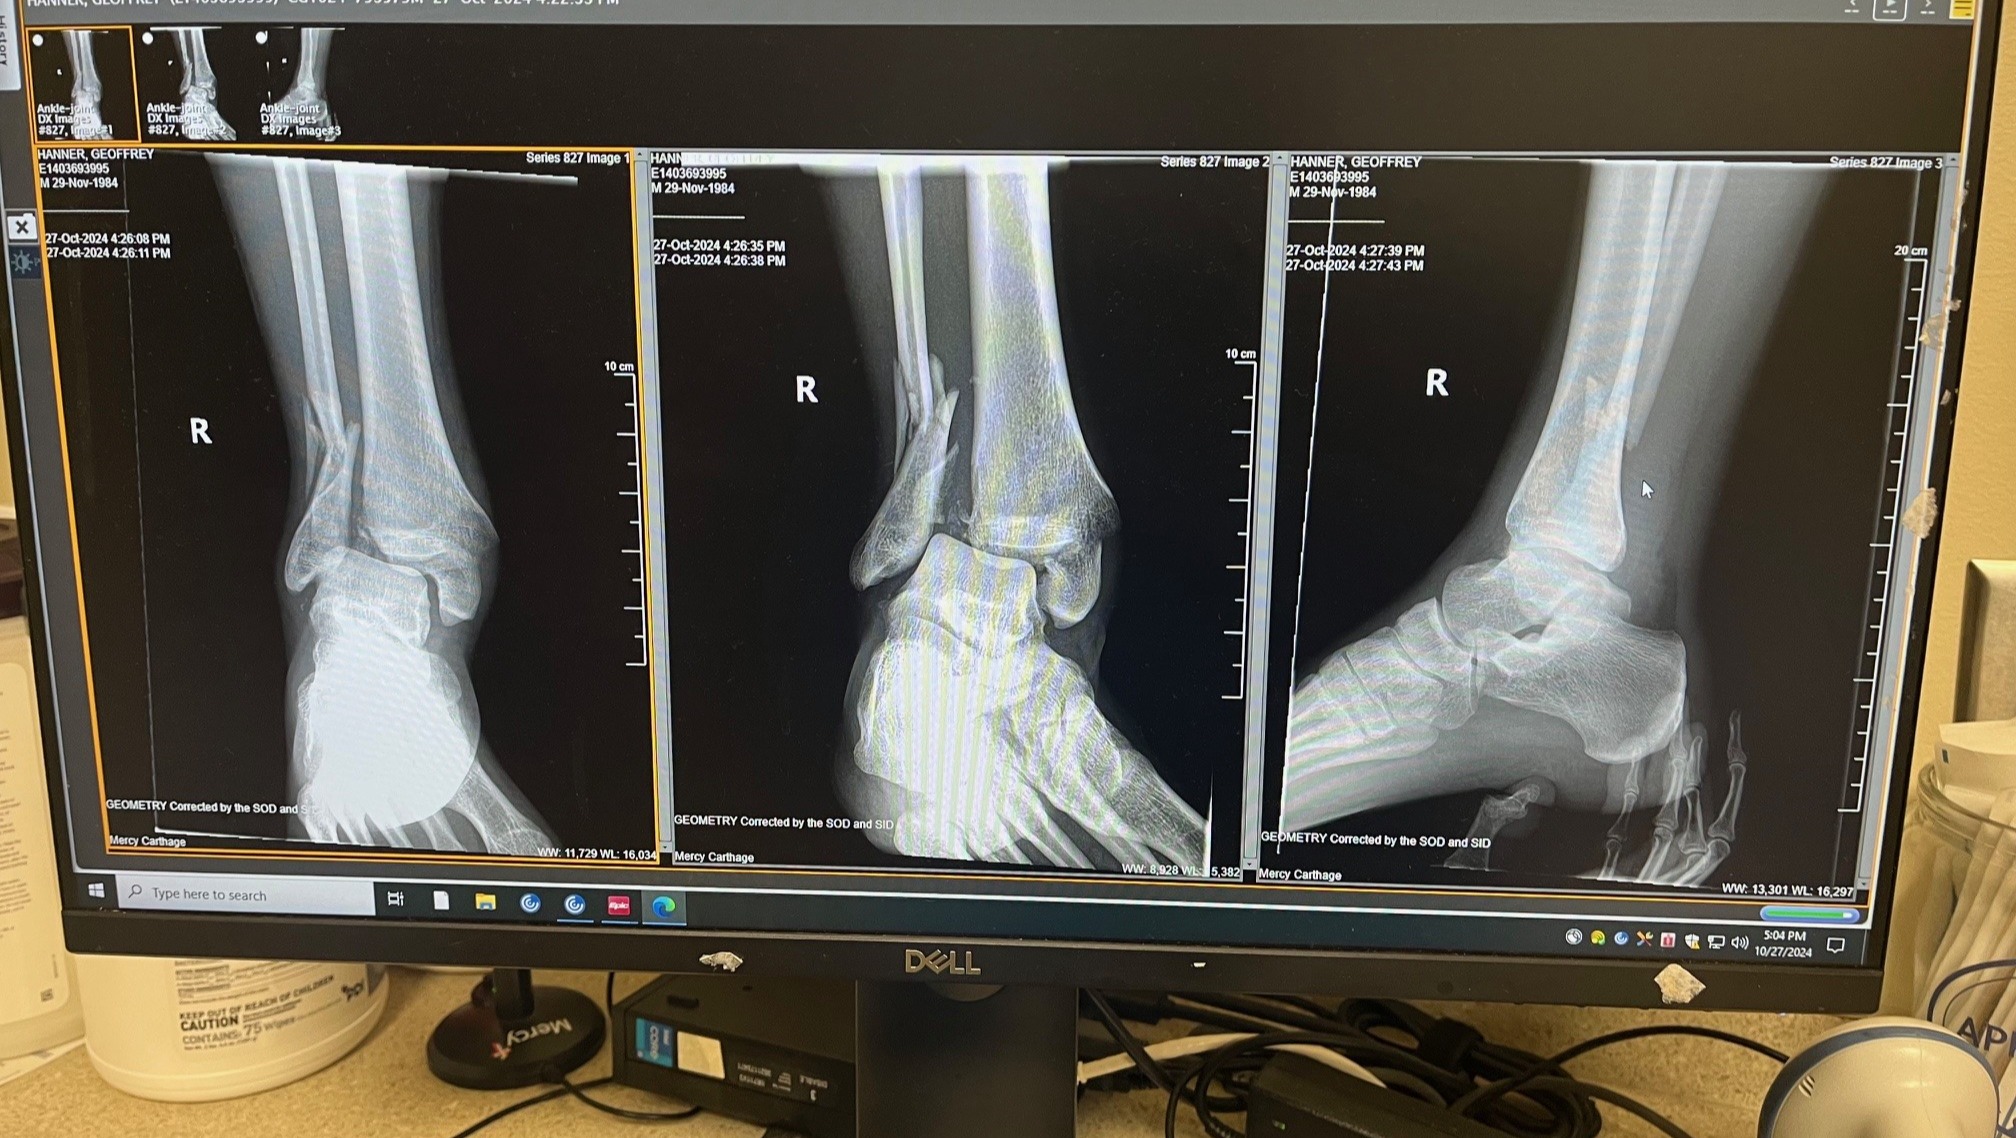

Geoff's prognosis is good right now, with a second surgery scheduled in November. He has broken / shattered parts of the distal tubular and fibula as a result of a mule-related accident but he's in good spirits and looking forward to getting back on his feet!